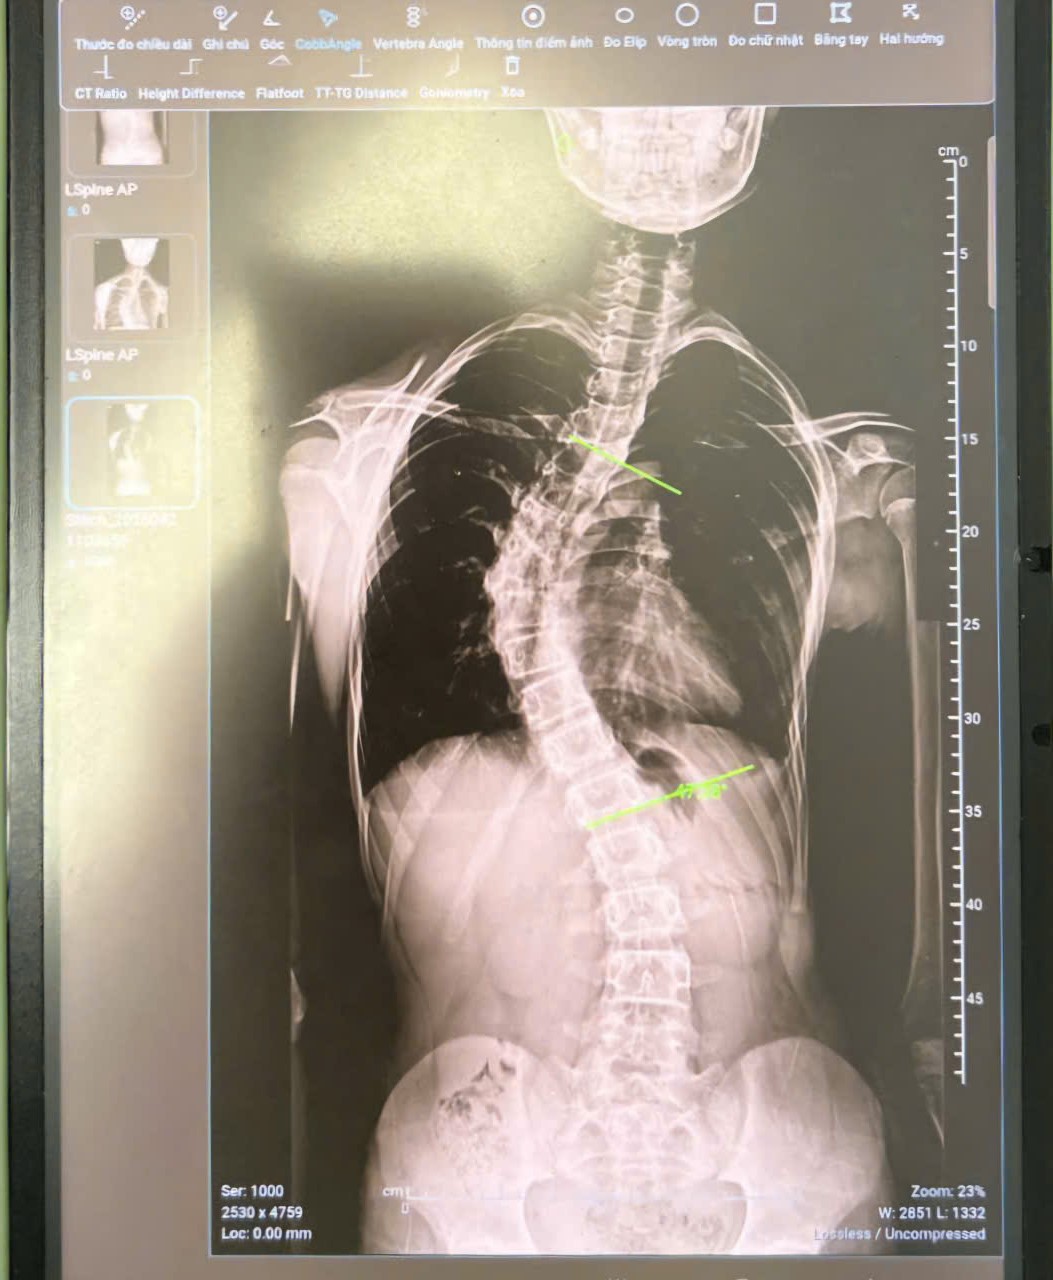

Tổng hợp các trường hợp điều trị cong vẹo cột sống – phương pháp áo nẹp chỉnh hình nắn chỉnh cột sống

*** Cú lội ngược dòng siêu đỉnh- thoát mổ vĩnh viễn với áo nẹp chỉnh hình nắn chỉnh cong vẹo cột sống  Gặp lại người xưa vui hơn cả ...

3+ nguyên nhân bệnh cong vẹo cột sống và cách điều trị

Yếu tố then chốt quyết định cách điều trị bệnh cong vẹo cột sống phù hợp và hiệu quả là gì? Trong khi thực trạng bệnh nhân mắc chứng ...